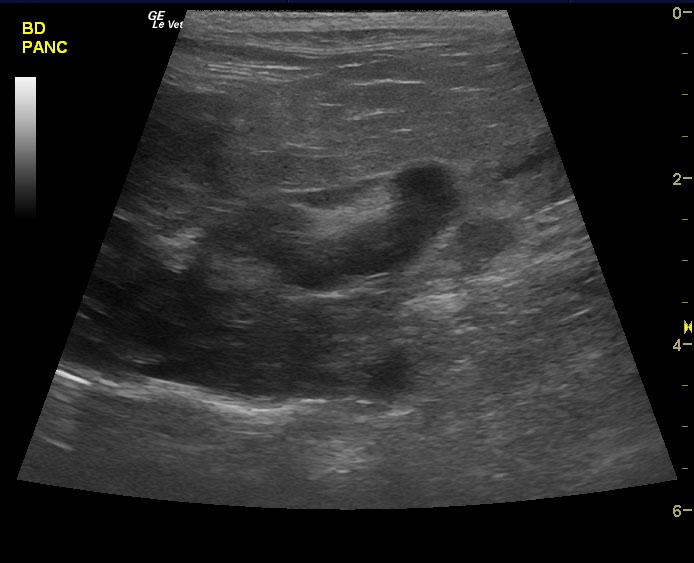

A 10-year-old, SF DSH cat was presented for acute onset vomiting and dehydration. Abnormalities on physical examination were icterus and dehydration. Pyuria with low urine SG was present on urinalysis. Urine culture was negative for bacterial growth after 24hrs. CBC and serum biochemistry showed marked leukocytosis with left shift and azotemia. Diffuse intestinal ileus was evident on survey radiographs.